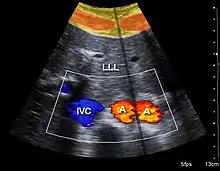

Both abdominal and endoanal ultrasound are frequently used in gastroenterology and colorectal surgery. In abdominal sonography, the major organs of the abdomen such as the pancreas, aorta, inferior vena cava, liver, gall bladder, bile ducts, kidneys, and spleen may be imaged. However, sound waves may be blocked by gas in the bowel and attenuated to differing degrees by fat, sometimes limiting diagnostic capabilities. The appendix can sometimes be seen when inflamed (e.g.: appendicitis) and ultrasound is the initial imaging choice, avoiding radiation if possible, although it frequently needs to be followed by other imaging methods such as CT. Endoanal ultrasound is used particularly in the investigation of anorectal symptoms such as fecal incontinence or obstructed defecation. It images the immediate perianal anatomy and is able to detect occult defects such as tearing of the anal sphincter.

Doppler ultrasonography is used to study blood flow and muscle motion. The different detected speeds are represented in color for ease of interpretation, for example leaky heart valves: the leak shows up as a flash of unique color. Colors may alternatively be used to represent the amplitudes of the received echoes.